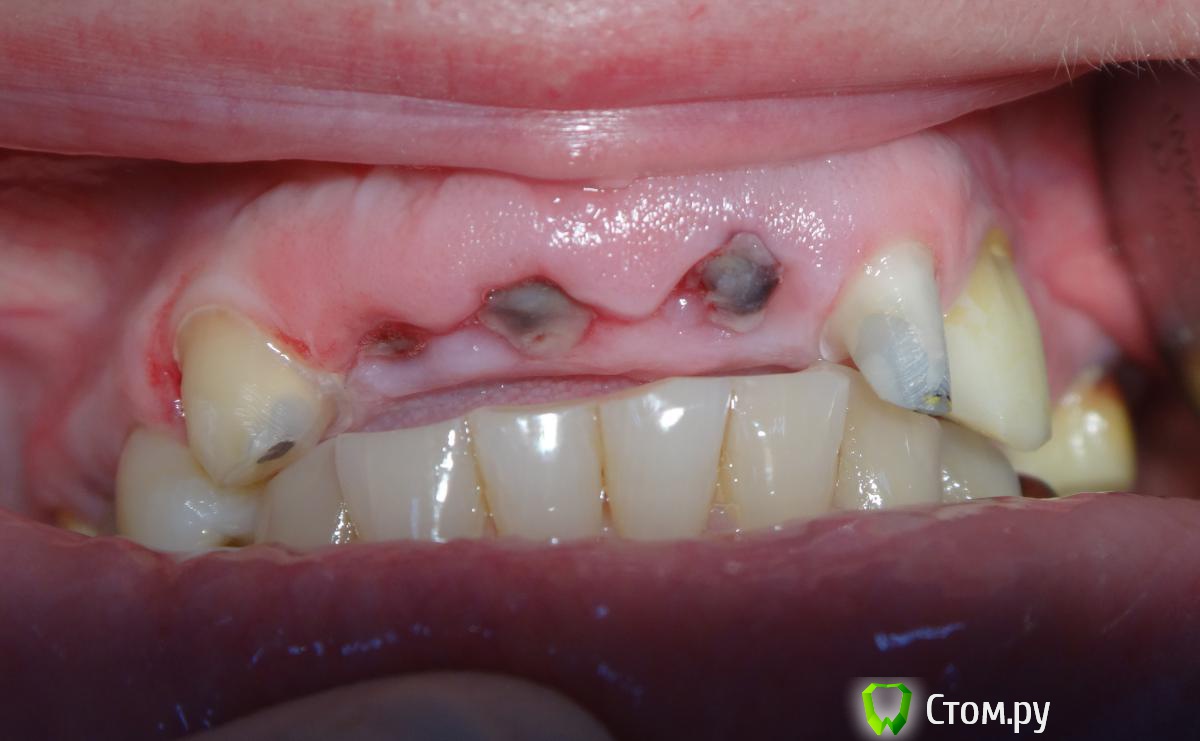

Slaggy Опубликовано 11 сентября, 2014 Поделиться Опубликовано 11 сентября, 2014 (изменено) Если планируется удаление переднего зуба, то стараемся одномоментно установить имплантат. Если это невозможно или нельзя нагружать винт, то делаем адгезивный "мериленд". Если пролёт в несколько зубов, то только съёмное. Можно дополню?Если пролет в несколько зубов, но ограничивающие деффект зубы будут обтачиваться, то можно армировать времянки металлом.вторую фотку перезагружаю:Это как раз на 3-4 день овоиды сделаны. первая фотка на 3-4 день после 3-4 дня после удаления.Что скажите мне изменится в поверхностных слоях сгустка и окружающих их тканей за 3-7 дней? Прорастет чем? или что?Нифига не вижу разницы одномоментно или на 3 день. Ааа. Есть разница. Не кровит и можно работать.А еще пациент осознав потерю значимей оценит обретение. Если удаляемый зуб имеет коронку, то можно его использовать для времянки.Извините за качество, не успел отфоткать - фотик сдох, успел пару раз нажать на затвор без подготовки.Вся центральная группа с клиновидными деффектами и подвижна, 21 - выдвинут на 3,5 мм. пациент не хочет с ним расстоваться, держит губами, оберегает.Нужен был быстрый "ход конем", чтоб он на шею не сел. Я пообещал за час сделать лучше чем есть. Пальцами удалил 21, обрезал под овоид, ретроградно запломбировал жидкотекучим, им же залил клиновидный и приклеил, армировав стекловолоконной лентой.Говенная работа, но она позволит мне дальше человека вывести на нормальное лечение.Вообще данный товрисч очень тяжелый, там все под бульдозер, а потом...Еще рас сорри за жесть, но это жизнь, работа, будни ))))) Изменено 11 сентября, 2014 пользователем Slaggy Ссылка на комментарий

chervoncevdaniil Опубликовано 11 сентября, 2014 Поделиться Опубликовано 11 сентября, 2014 Можно дополню?Если пролет в несколько зубов, но ограничивающие деффект зубы будут обтачиваться, то можно армировать времянки металлом.DSC00368.JPGDSC00336.JPGDSC00338.JPGвторую фотку перезагружаю:DSC00345.JPGЕсли удаляемый зуб имеет коронку, то можно его использовать для времянки.DSC00501.JPGDSC00502.JPGИзвините за качество, не успел отфоткать - фотик сдох, успел пару раз нажать на затвор без подготовки.Вся центральная группа с клиновидными деффектами и подвижна, 21 - выдвинут на 3,5 мм. пациент не хочет с ним расстоваться, держит губами, оберегает.Нужен был быстрый "ход конем", чтоб он на шею не сел. Я пообещал за час сделать лучше чем есть. Пальцами удалил 21, обрезал под овоид, ретроградно запломбировал жидкотекучим, им же залил клиновидный и приклеил, армировав стекловолоконной лентой.Говенная работа, но она позволит мне дальше человека вывести на нормальное лечение.Вообще данный товрисч очень тяжелый, там все под бульдозер, а потом...Еще рас сорри за жесть, но это жизнь, работа, будни )))))тут прикус будете поднимать?просто по фото 13 в контакте с антагонистом или мне кажется? Ссылка на комментарий

Slaggy Опубликовано 11 сентября, 2014 Поделиться Опубликовано 11 сентября, 2014 (изменено) тут прикус будете поднимать?просто по фото 13 в контакте с антагонистом или мне кажется?На фото внизу еще отсвечивают штампованные мостывсе разобираем - жевательные низ и верх снимаемда прикус повышаем Это. кстати, одна из любимых частей профессии - приходит дама с зубами, а уходит с улыбкой. ))))) А вот и не вспомнил я ответа про контакт на 13. ))))Там сейчас кроме этого понтика зубов почти и нет в контакте. Изменено 11 сентября, 2014 пользователем Slaggy Ссылка на комментарий